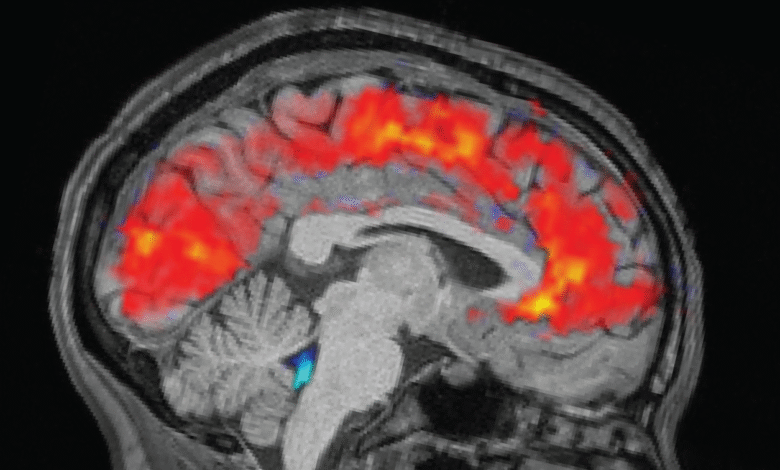

Odpočatí jedinci spali 6,5 až 9 hodin doma, zatímco nevyspalí jedinci byli v laboratoři udržováni vzhůru celou noc. Ráno před každým pokusem tým účastníkům připevnil elektroencefalogramové (EEG) čepice, aby pomocí elektrod zaznamenal jejich mozkové vlny. Současně účastníci podstoupili funkční MRI (fMRI) skenuje k odhalení vzorců v průtoku krve a CSF v mozku. Eye-trackery měřily velikost zornic účastníků.

Jak se očekávalo, účastníkům trvalo déle, než si všimli podnětů, když byli unavení, a častěji jim chyběla narážky, než když byli dobře odpočatí. Ale tým byl překvapen, když u vyčerpaných jedinců uviděl obří pulsy mozkomíšního moku spolu se vzorem pomalých mozkových vln – které jsou normálně pozorovány v non-REM spánku.

Konkrétně se vzory podobaly tomu, z něhož se člověk posouvá fáze N1 do N2první dvě ze tří fází non-REM spánku, které lidé zažívají každý spánek. „Bylo to něco, co jsme dříve v tomto měřítku viděli pouze během spánku,“ řekl Lewis.

Vědci se domnívají, že mozkové vzorce, které vidí, mohou odrážet, jak se mozek s nedostatkem spánku posouvá do stavu podobného spánku, ale zatímco je stále vzhůru. Výpadky pozornosti signalizují začátek těchto mozkových procesů podobných spánku, ale ty jsou přerušeny, než nastane správný spánek.